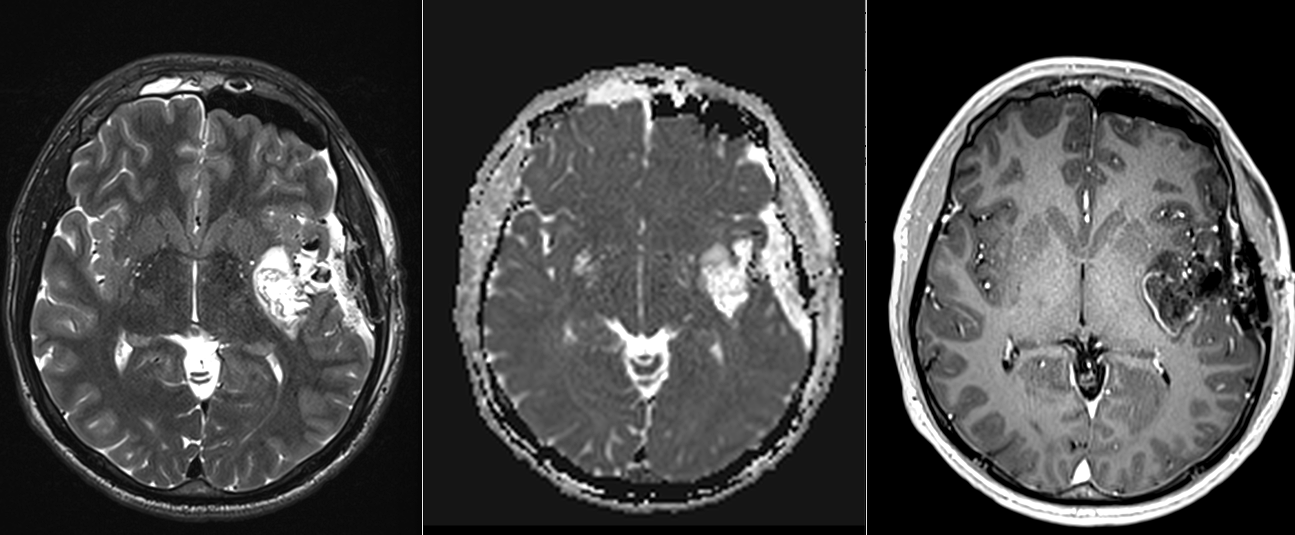

RMN cerebral cu contrast – metoda standard pentru caracterizarea glioamelor. Glioamele de grad mic apar ca leziuni hipointense pe T1, hiperintense pe T2, fără captare de contrast. În mod uzual se consideră că dacă un gliom de grad mic are o zonă cu priză de contrast pe RMN el este de grad III – anaplazic (grad înalt).

Spectroscopie RMN și perfuzie cerebrală – pot oferi informații suplimentare despre agresivitate.

Oligodendrogliom temporal stâng – spectroscopie RMN

– CT cerebral – util doar ca evaluare inițială; are sensibilitate scăzută și poate trece frecvent cu vederea o tumora de dimensiuni reduse.

Gliom de grad mic de hipocamp stâng – comparație CT – RMN